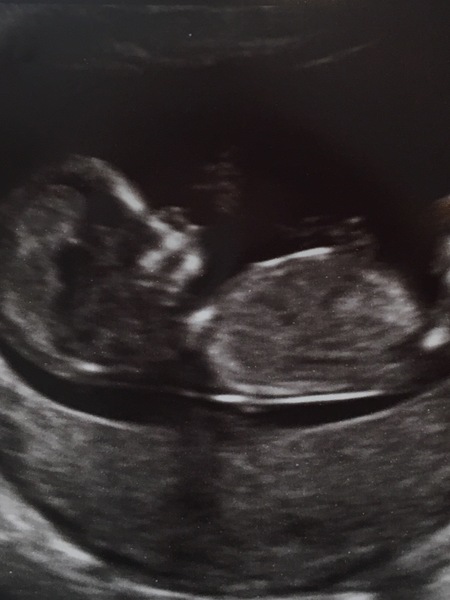

Teachervoice · 14/05/2017 12:16

Here's mine again, without the details! Haha!

Oh, @izzibee29 I did that too! Had to take my scan pic off but was so excited to post that I forgot to remove details!